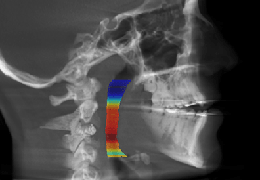

ANYTHINK 经导管主动脉瓣膜置换术分析系统